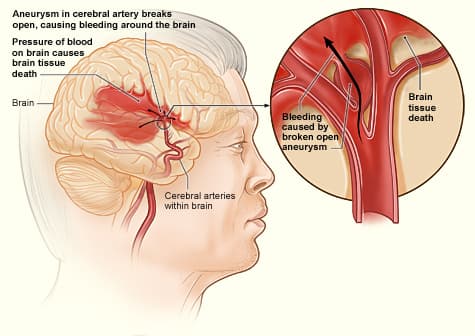

Reverse Hemorrhage Stroke Degeneration Naturally